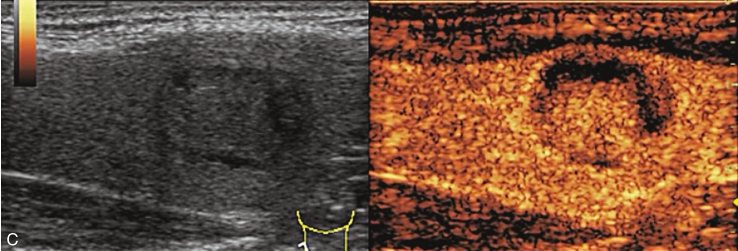

男性,64岁,体检发现甲状腺结节1天。体格检查:甲状腺无明显肿大。

甲状腺左叶中部实性中等回声,边缘光整,纵横比<1,内未见明显强回声,CDFI:结节内见血流信号,见图1-3-9。

图1-3-9 结节性甲状腺肿常规超声声像图

A.甲状腺左叶纵切面;B.CDFI血流图

甲状腺左叶中部结节15s开始增强。增强早期与周围正常甲状腺组织呈同步等增强,内部增强不均匀,增强后结节边界清,形态规则,周边可见环状高增强,增强晚期呈不均匀性低增强,见图1-3-10、ER1-3-5。

结节性甲状腺肿超声造影表现为病变多与周围正常甲状腺组织呈同步等或高增强,增强多较均匀,伴有囊性变者,内部可见无增强区,增强后结节边界清,周边可见环状增强,增强晚期呈等或稍高增强,也可呈稍低增强。